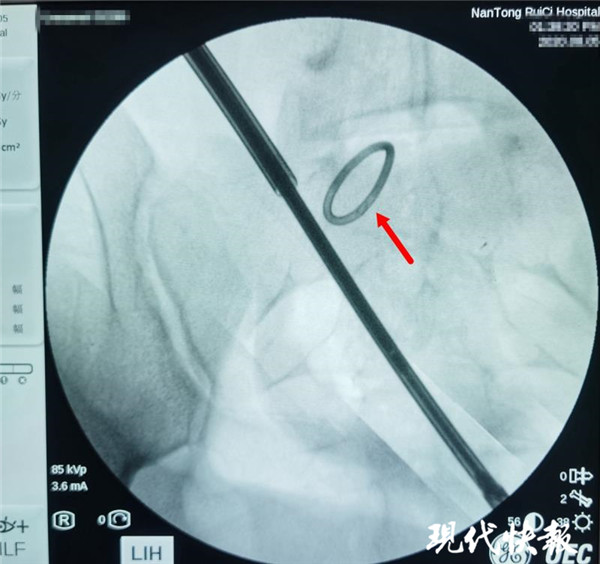

△術(shù)中X光,可清晰看到節(jié)育環(huán)

通過反復(fù)的X光定位,醫(yī)生終于發(fā)現(xiàn)了節(jié)育環(huán)的蹤跡,這枚“O”型節(jié)育環(huán)已經(jīng)跑到了乙狀結(jié)腸中段右側(cè)系膜內(nèi),并且穿透了乙狀結(jié)腸右側(cè)壁肌層,貫穿腸腔。醫(yī)生分離切開腸系膜后,看見有近一半的節(jié)育環(huán)嵌頓在腸腔內(nèi)。之后胡偉和吳忠新相互配合,將節(jié)育環(huán)完整取出,并根據(jù)術(shù)中談話時(shí)患者家屬選擇的手術(shù)方案,對腸壁的兩處瘺孔進(jìn)行了修補(bǔ)縫合,手術(shù)順利結(jié)束。